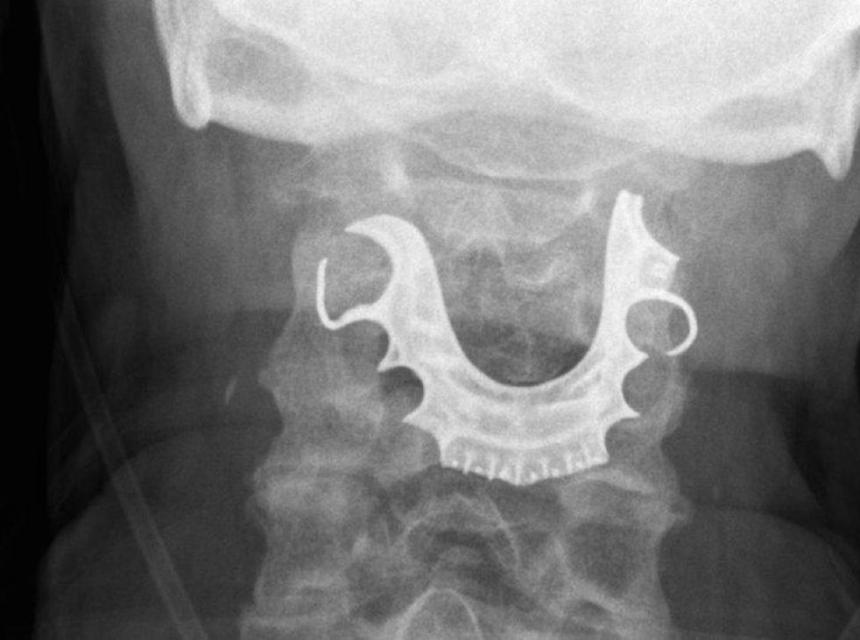

Kada se muškarac dva dana kasnije ponovo javio kod lekara, medicinsko osoblje pregledalo je grlo i glasne žice - i pronašlo polukružni predmet koji leži preko njih.

On je lekarima rekao da je za vreme operacije u bolnici izgubio protezu.